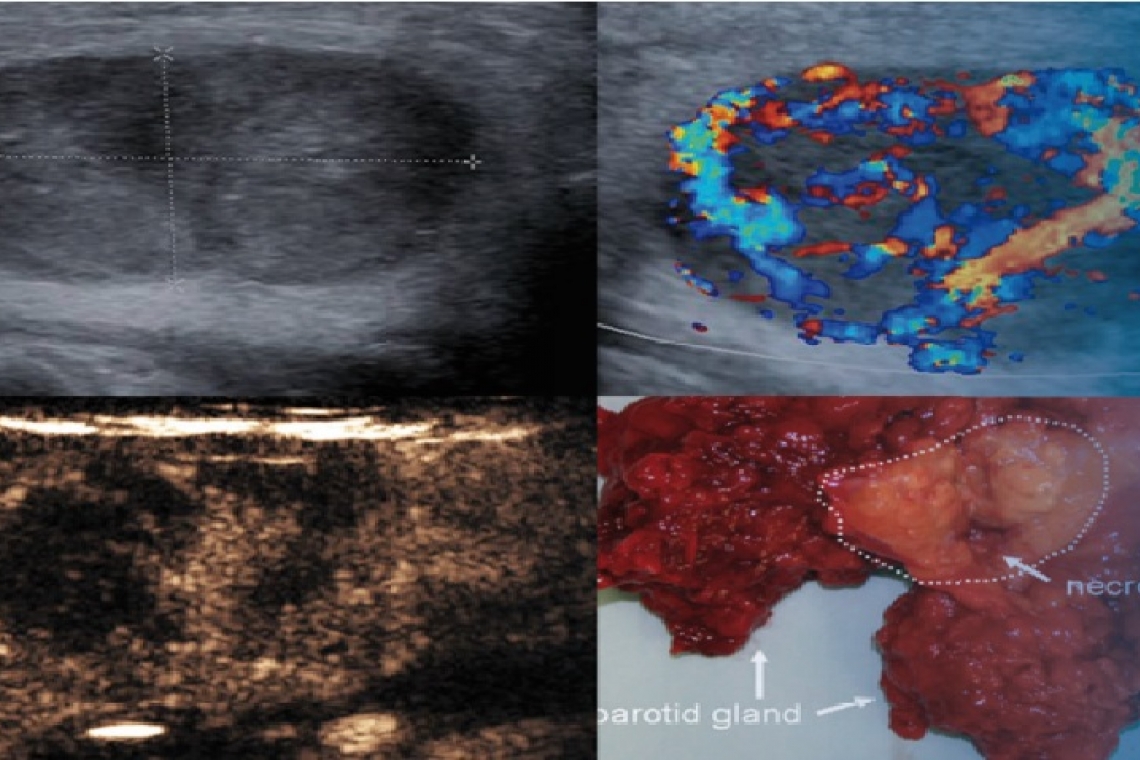

In der Abklärung von vielen verschiedenen Erkrankungen im Bereich der Speicheldrüsen ist die Sonographie das wichtigste bildgebende Verfahren. Entsprechend des Kurscurriculums der Sektion Kopf-Hals der Deutschen Gesellschaft für Ultraschall in der Medizin (DEGUM) deckt dieser Kurs alle relevanten Aspekte der Speicheldrüsensonographie ab. Der Kurs eignet sich sowohl für Einsteiger in die Kopf-Hals-Sonographie, aber auch für erfahrende Kolleginnen und Kollegen, die ihr Wissen auf dem Gebiet der Speicheldrüsensonographie noch vertiefen wollen. Zusammen mit einem weiteren Modul (wie zum Beispiel das von uns einmal jährlich angebotenen Modul Farbduplex- und Dopplersonographie) kann dieser Kurs als Alternative zu einem DEGUM-Abschlusskurs absolviert werden. Dieser Kurs wird als rein virtueller Kurs geplant und beinhaltet anstelle von praktische Übungen eine praxisorientierte Wissensvermittlung.